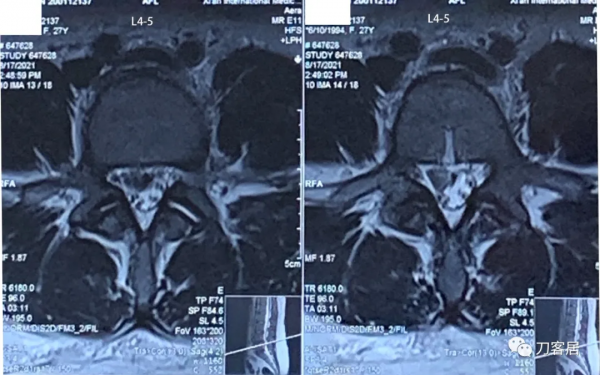

圖5. 20210817術前腰椎MRI橫截面掃描提示L3-4椎間盤輕度突出,左側旁中央型。

圖6. 20210817術前腰椎MRI橫截面提示L4-5椎間盤突出,較大,右旁側型。